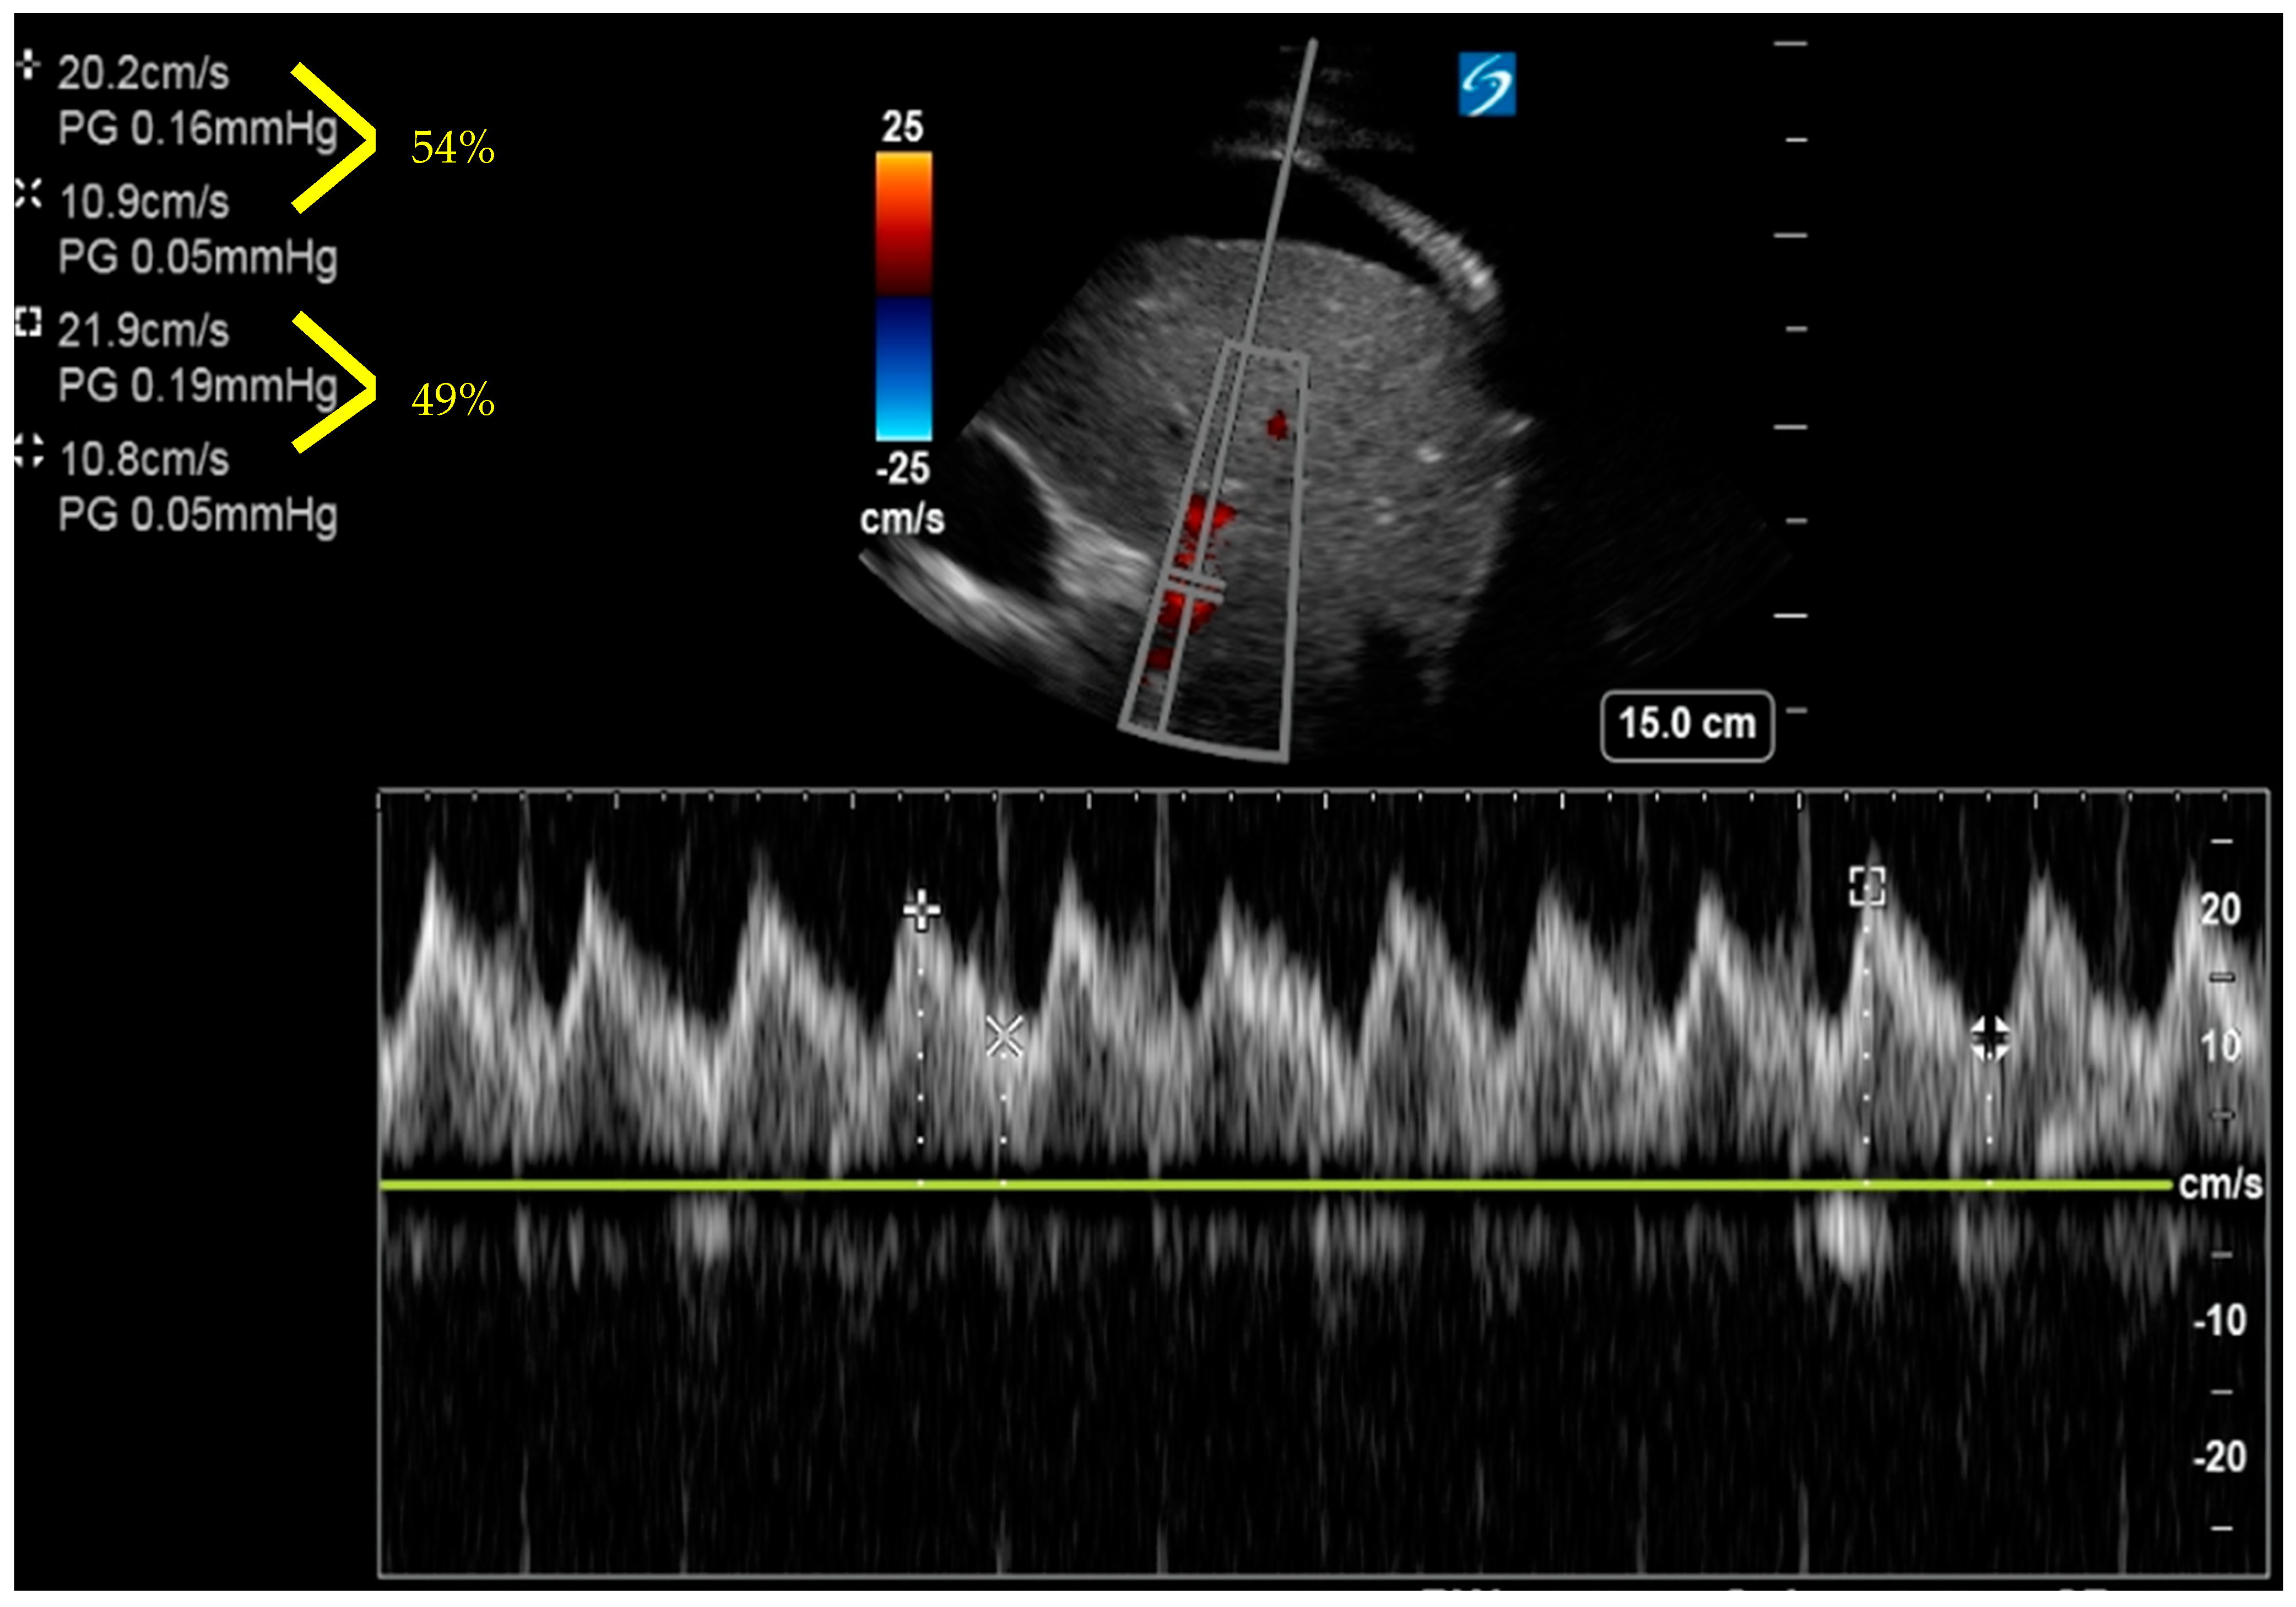

6. Venous Excess Ultrasound Score